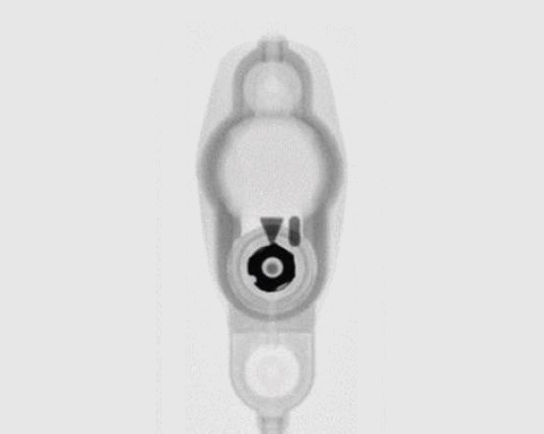

Spitz Holter

Spitz-Holter valves are non-programmable csf shunt valves introduced in 1956.